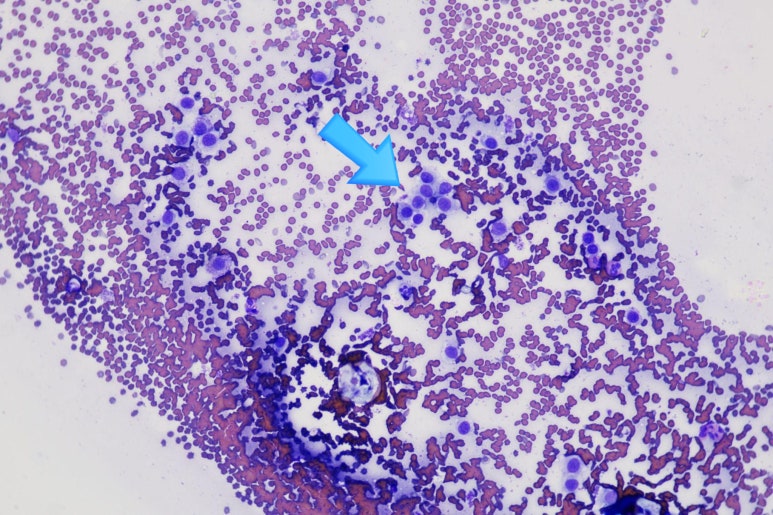

▲ 본원에서 실시한 세포 검사 현미경 사진입니다.

파란색 화살표가 가리키는 것들이 모두 비만세포(Mast cell)들입니다.

보라색 세포질 과립을 가득 머금은 비만세포들이 유의미하게 대량으로 관찰되는 것을 볼 수 있습니다.

이 검사 결과를 바탕으로, 아이를 3년간 괴롭혔던 과잉 그루밍의 진짜 원인은 단순 피부염이 아닌 '피부 비만세포종(Cutaneous Mast Cell Tumor, MCT)'으로 진단되었습니다.